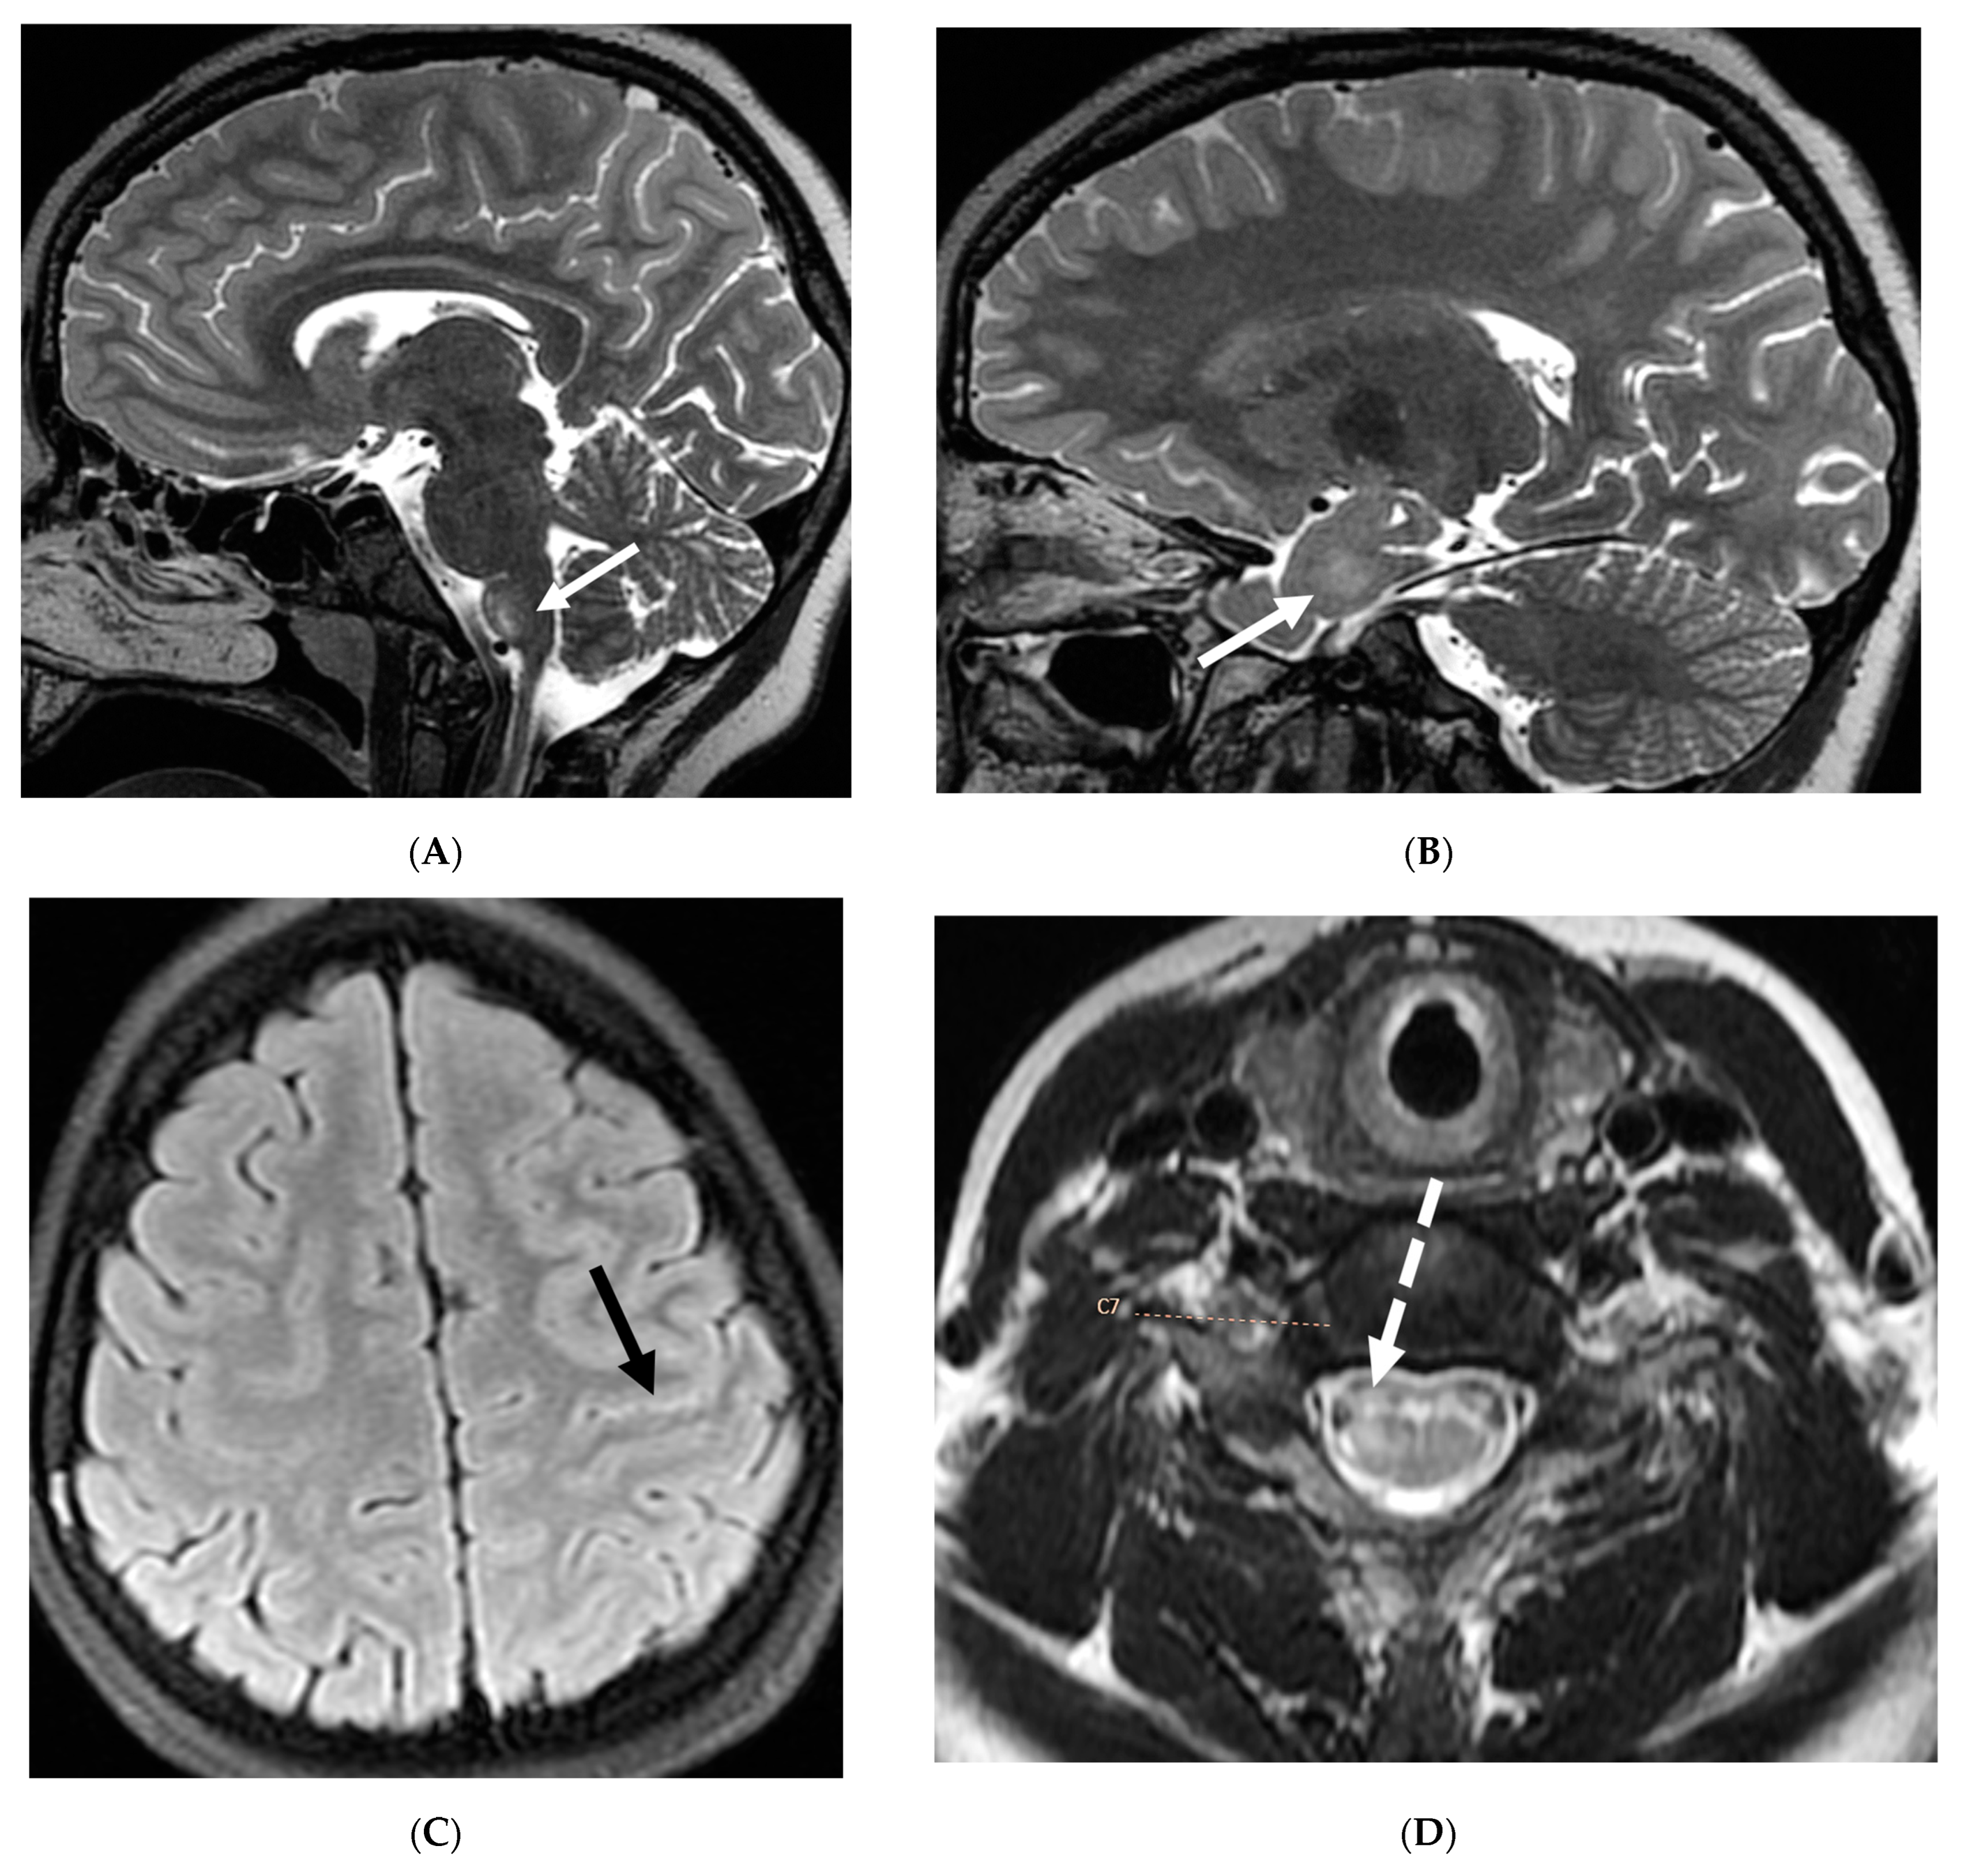

5.4. Granulomatosis Polyarteritis (GPA)

GPA is an autoimmune necrotizing granulomatous inflammation associated with anti-neutrophil cytoplasmic antibody (ANCA) vasculitis. This multisystem disorder predominantly affects small vessels, causing endothelial injury and tissue damage in the upper and lower respiratory tract and renal system [109,110]. Neurologic involvement occurs in 20–50% of GPA patients, mediated by three main mechanisms: vasculitis of cerebral vessels, granuloma formation due to contiguous involvement from adjacent paranasal and orbital lesions, and remote granulomatous lesions in brain parenchyma or meninges [111,112]. Patients typically present with headache, altered mental status, and transient ischemic attacks. Pituitary gland involvement can manifest as hyperprolactinemia or diabetes insipidus [111].

Imaging findings in GPA include chronic hypertrophic pachymeningitis (most common) representing granulomatous involvement. This can be diffuse or focal, with the latter showing dural thickening and enhancement adjacent to a sinus or orbit [113]. Tentorium involvement is common, presenting as the ‘Eiffel by night’ sign [114]. Cerebral vasculitis appears as multiple T2 hyperintense white matter lesions potentially showing diffusion restriction and patchy enhancement. Cerebral atrophy may be observed, attributed to steroid treatment and/or vasculitis. Pituitary involvement can range from normal to enlarged gland size, with thickened stalk and peripheral enhancement. Cranial nerve involvement, particularly of the olfactory and optic nerves, is common due to mass effect from adjacent lesions or hypertrophic pachymeningitis (Figure 22) [112].

Figure 22.

Post contrast axial FLAIR (A), axial T1 FS (B), sagittal T1 Right (C) and Left (D): 10-year-old girl with elevated ANCA, headache and mild LUE weakness. There is bilateral anterior temporal smooth dural enhancement (white arrows). Diagnosis: Antineutrophilic cytoplasmic antibody (ANCA) associated vasculitis, likely granulomatosis with polyangiitis.